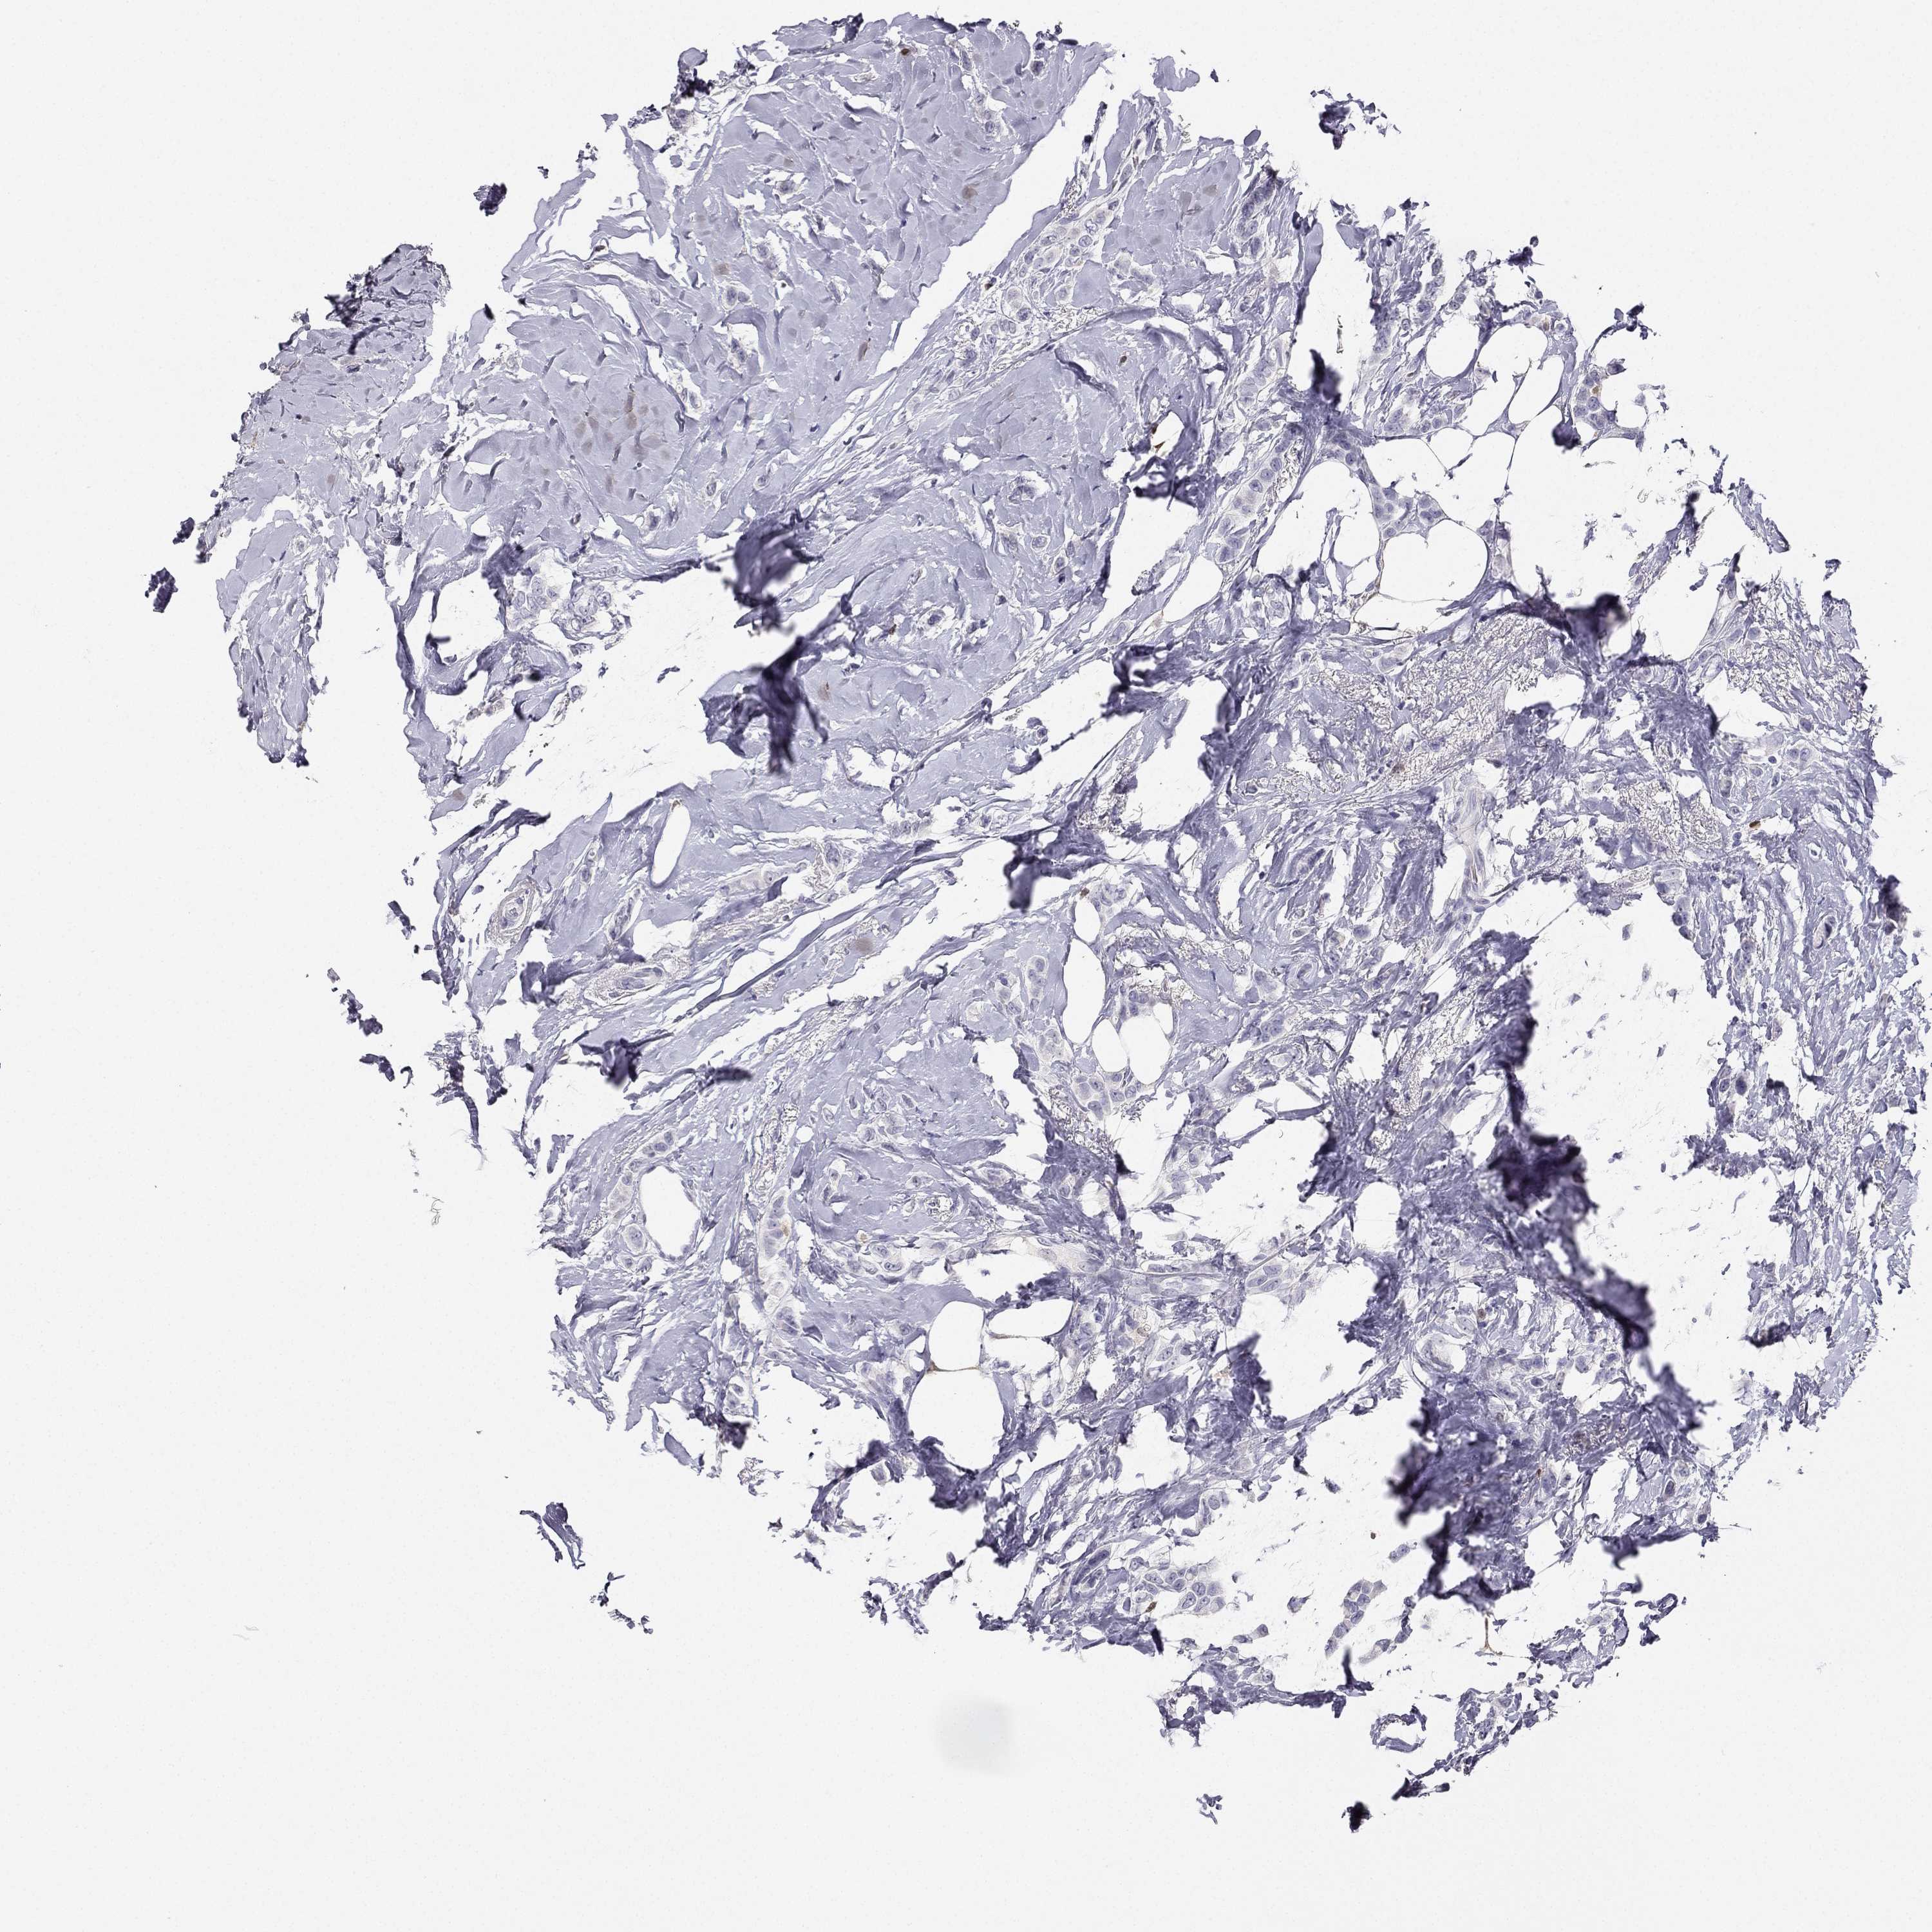

CANCER BREAST CANCER Show tissue menu

BRCA TCGA BRCA VALIDATION PROTEIN EXPRESSION